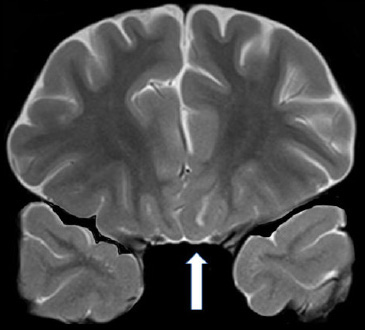

Functional connectivity between the right amygdala and anterior vmPFC is reduced in psychopaths. From Fig. 2 of Motzkin et al., (2011).